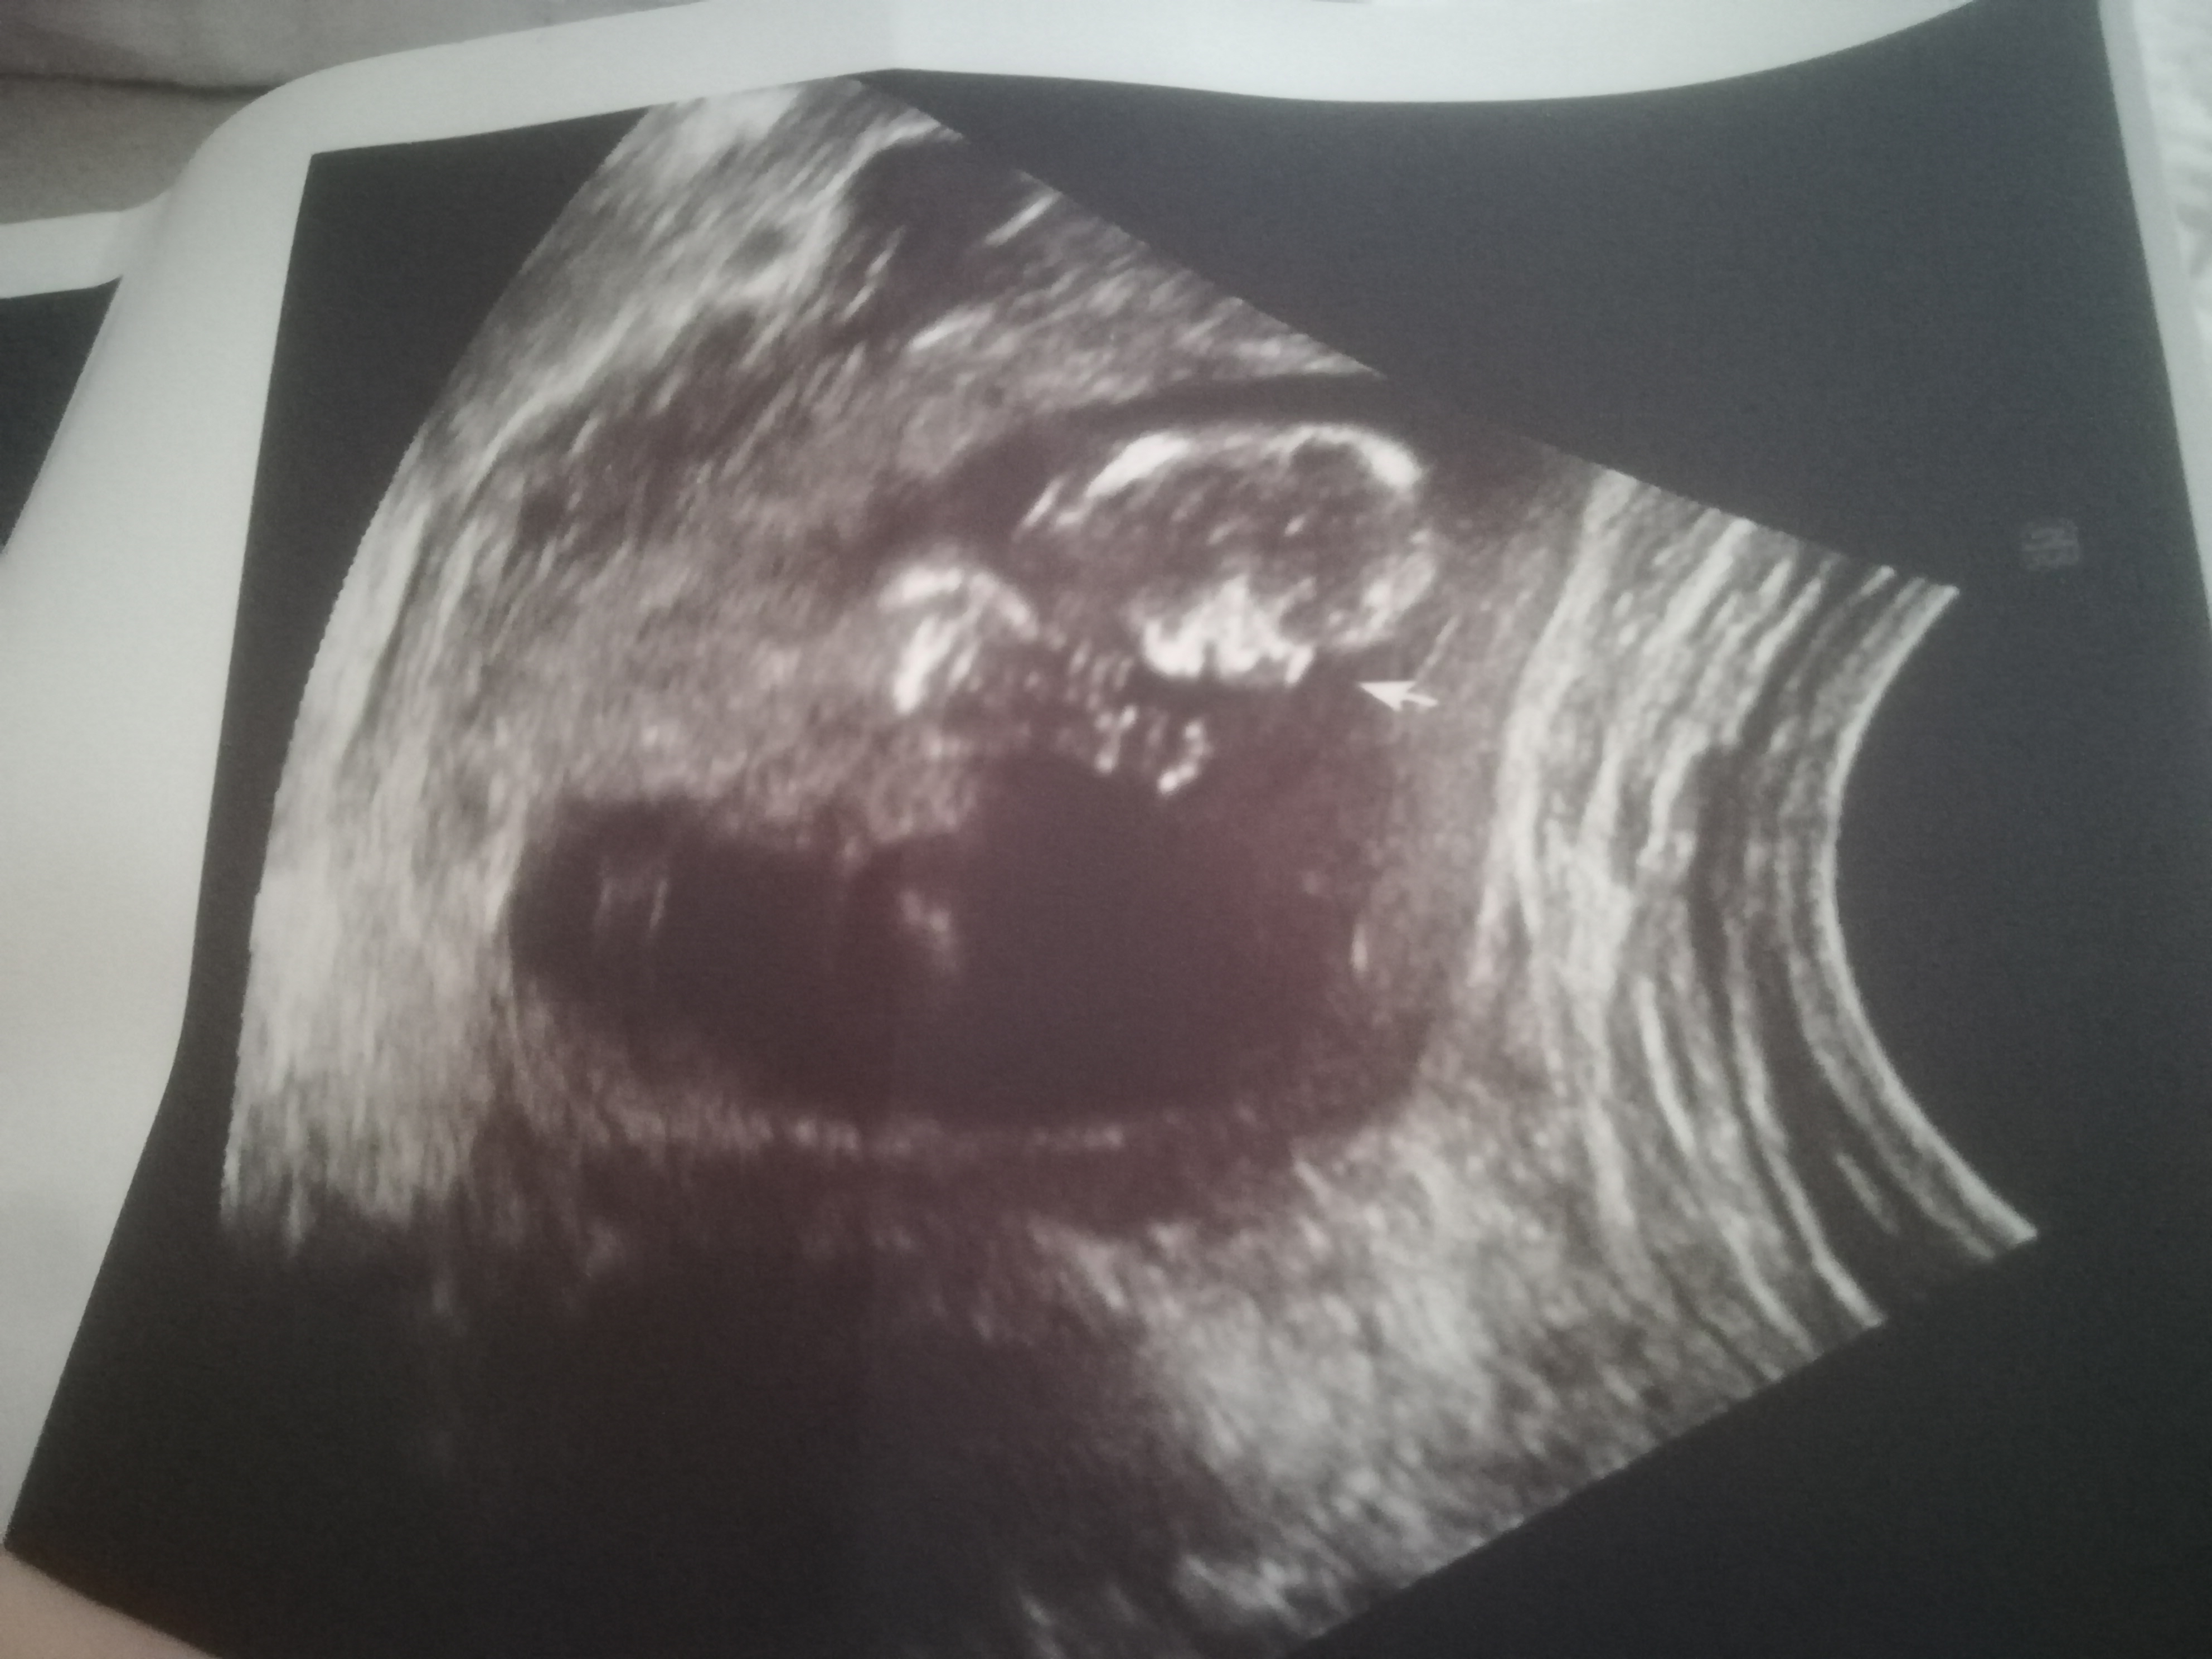

Cinsiyet tahmini yapabilir misiniz banada çok merak ediyorum 10+6 yiz burada

Ekli dosyalar

• IMG_20211108_210352.jpg

IMG_20211108_210352.jpg

1,6 MB · Görüntüleme: 265

Selamlar dilayım cevap yazdım ultrason sonucu nub teorisine göre cinsiyet tahmini için yetersiz geldi hayatım. Yani başka resim var ise ekleyin yok ise ben tercihimi kız demekten yana kullanıyorum.